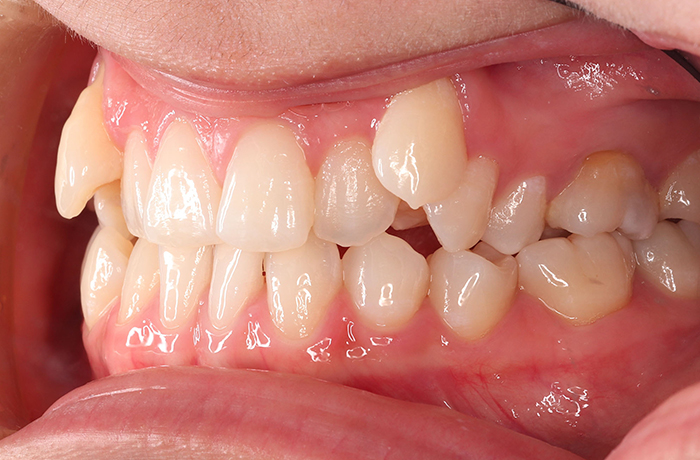

治療前

before

患者の症状 叢生、正中のずれ、上顎左右側切歯の口蓋側転位(交叉咬合)

治療方法 非抜歯で、マウスピース型カスタムメイド矯正歯科装置(インビザライン)による矯正

歯列弓を拡大することで非抜歯を可能にしました。

治療結果 側切歯の交叉咬合は解消、上下正中のずれも改善し咬み合わせが良くなりました。